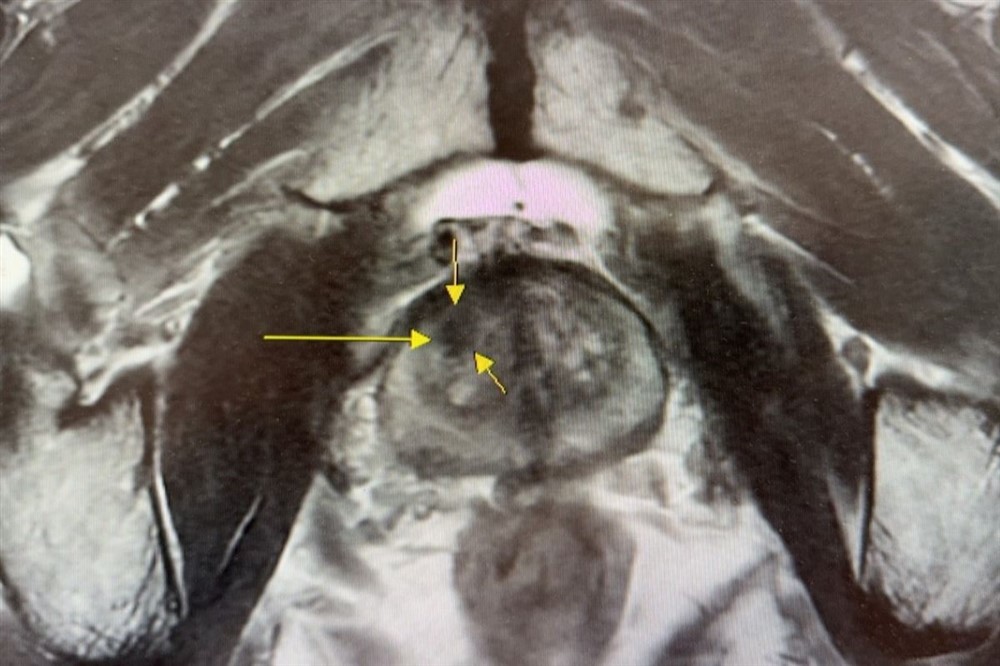

核磁造影與超音波影像融合攝護腺切片檢查,精準判斷腫瘤位置。圖/台北慈院提供

在早期診斷方面,台北慈濟醫院以「核磁造影與超音波影像融合攝護腺切片」,取代傳統「經直腸超音波攝護腺切片」,利用3D 影像融合技術將核磁造影顯示的病灶與超音波重疊,讓切片檢查不再是隨機,避免誤判良性或需要重複切片的情形發生。這樣的改變,讓切片準確率提升六至七成,病人得以在早期病灶尚未擴散、轉移時就接受手術治療,平均五年存活率高達九成;而在治療挑戰最高的末期患者中,台北慈院第四期的五年存活率仍達近六成,整體成效遠高於全臺醫學中心。蔡曜州主任說明:「晚期攝護腺癌治療並非單一科別或單一療法可完成,團隊在治療策略上會依據病人確診期別、腫瘤侵犯範圍與身體狀況,整合泌尿科、放射腫瘤科等領域的專業人員,進行個人化治療。其中包括化學治療、放射線治療、賀爾蒙治療以及標靶藥物治療,延長存活期的同時,兼顧病人的生活品質。」